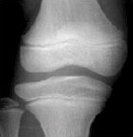

4) 같은 또래 아이들의 키보다 2표준편차 이상 작은 경우에는 성장클리닉 전문의의 진료가 필요합니다. 키가 정확히 또래 아이들보다 작은편인지 큰 편인지 진료를 통해 알아볼 수 있으며 성장판 촬영으로 골연령을 정확히 측정하는 것이 중요합니다.

| 열린경우 | 닫혀가는 경우 | 닫힌 경우 | |

| 경골 Tibia |